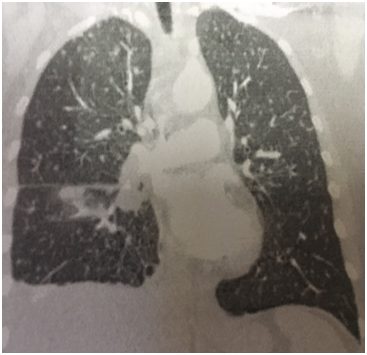

A 57 year old Caucasian female was admitted for dry cough, fever, loss of appetite and chest pain for three weeks. She had a history of tonsillectomy, ankylozing spondylitis, uveitis, pelvis fracture and tibia fracture. Her father died of colonic carcinoma. Her mother had hypertension and previous pulmonary tuberculosis. The patient was under treatment with certolizumab, methotrexate, and prednisolonefor ankylozing spondylitis and uveitis. Daily 300mg isoniazid was also given simultaneously with certolizumab for prophylaxis. Initial laboratory findings revealed WBC 8.2X103/mm3, hemoglobin 10.8g/dl, platelets 341X103mm3, lymphocytes 1.4X103/mm3, creatinine 0.74mg/dl, AST 18IU/L, ALT 18IU/Lmm3, LDH 167IU/L, albumine 3.56gr/dl, CRP 18.6 mg/dl, and calcium 9.1 mg/dl. ECG showed sinus ryhtm. Tuberculin test was negative. Chest x-rayshowed diffuse miliary nodules, alveolar infiltration in the right lower lobe, and right pleural effusion (Figure 1). Pleural protein 4.57g/dl, LDH 353U/L, and albumin 3.56g/dl. Pleural fluid had 1540cells/mm3 with a 74% lymphocyte ratio. Pleural fluid ADA was 114U/L (normal 0-40 U/L). The pleural fluid was exudative compatible with tuberculosis. Computed tomography of the thorax revealed diffuse miliary nodules, infiltration in the right anterior segment of the lower lobe, and right pleural effusion (Figures 2-4). Sputum stains was positive for acid-fast bacilli. Mycobacterium tuberculosis was isolated from the sputum culture. The final diagnosis was miliary tuberculosis associated with certolizumab occuring on the third month of treatment. The patient was commenced on pyrazinamide, isoniazid, rifampicine, and ethambutol treatment for tuberculosis while certolizumab treatment was stopped.

Figure 4 Axial computed tomography showing diffuse miliary nodules and right pleural effusion at the carenal level.